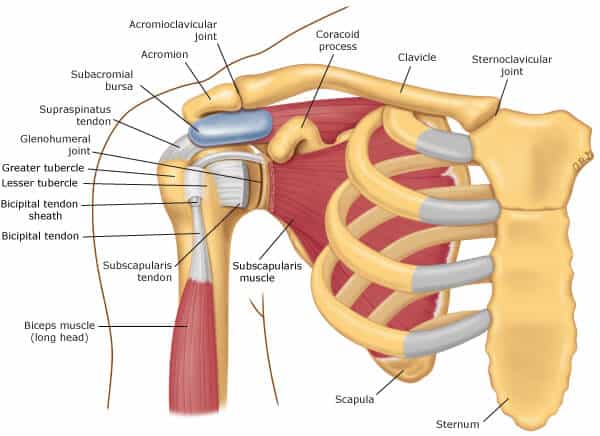

Anatomia do ombro

O complexo do ombro é constituído por músculos e articulações que possibilitam a movimentação do membro superior. É a articulação com maior mobilidade do corpo, mas também apresenta grande instabilidade devido à conformação da articulação glenoumeral, formada pela cabeça grande e arredondada do úmero e pela cavidade glenoidal pequena e côncava, o que reduz a coaptação articular.

Contudo, essa instabilidade é compensada pelos lábios articulares compostos pela cápsula articular e pelo tendão da cabeça longa do bíceps braquial, além da posição anatômica dos ligamentos coracoumerais e glenoumerais, bem como pela tensão exercida pelos tendões dos músculos do manguito rotador.

O manguito rotador, por sua vez, é formado pelos tendões dos músculos subescapular, supraespinhal, infraespinhal e redondo menor, cujas principais funções serão revisadas a seguir.